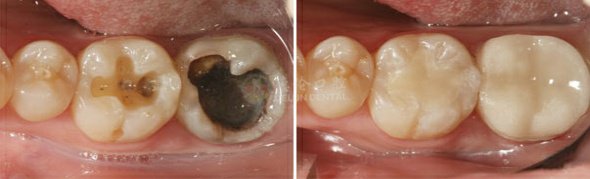

2. 嵌体修复:根据牙齿缺损部位窝洞的形状,用全瓷制作出来相应的修复体,粘结在缺损部位。

适应症: 各种牙体缺损较为严重,嵌体修复耐磨,不脱落无需二次充填,使用年限较长,多用于后牙修复。

修复技术:瓷嵌体